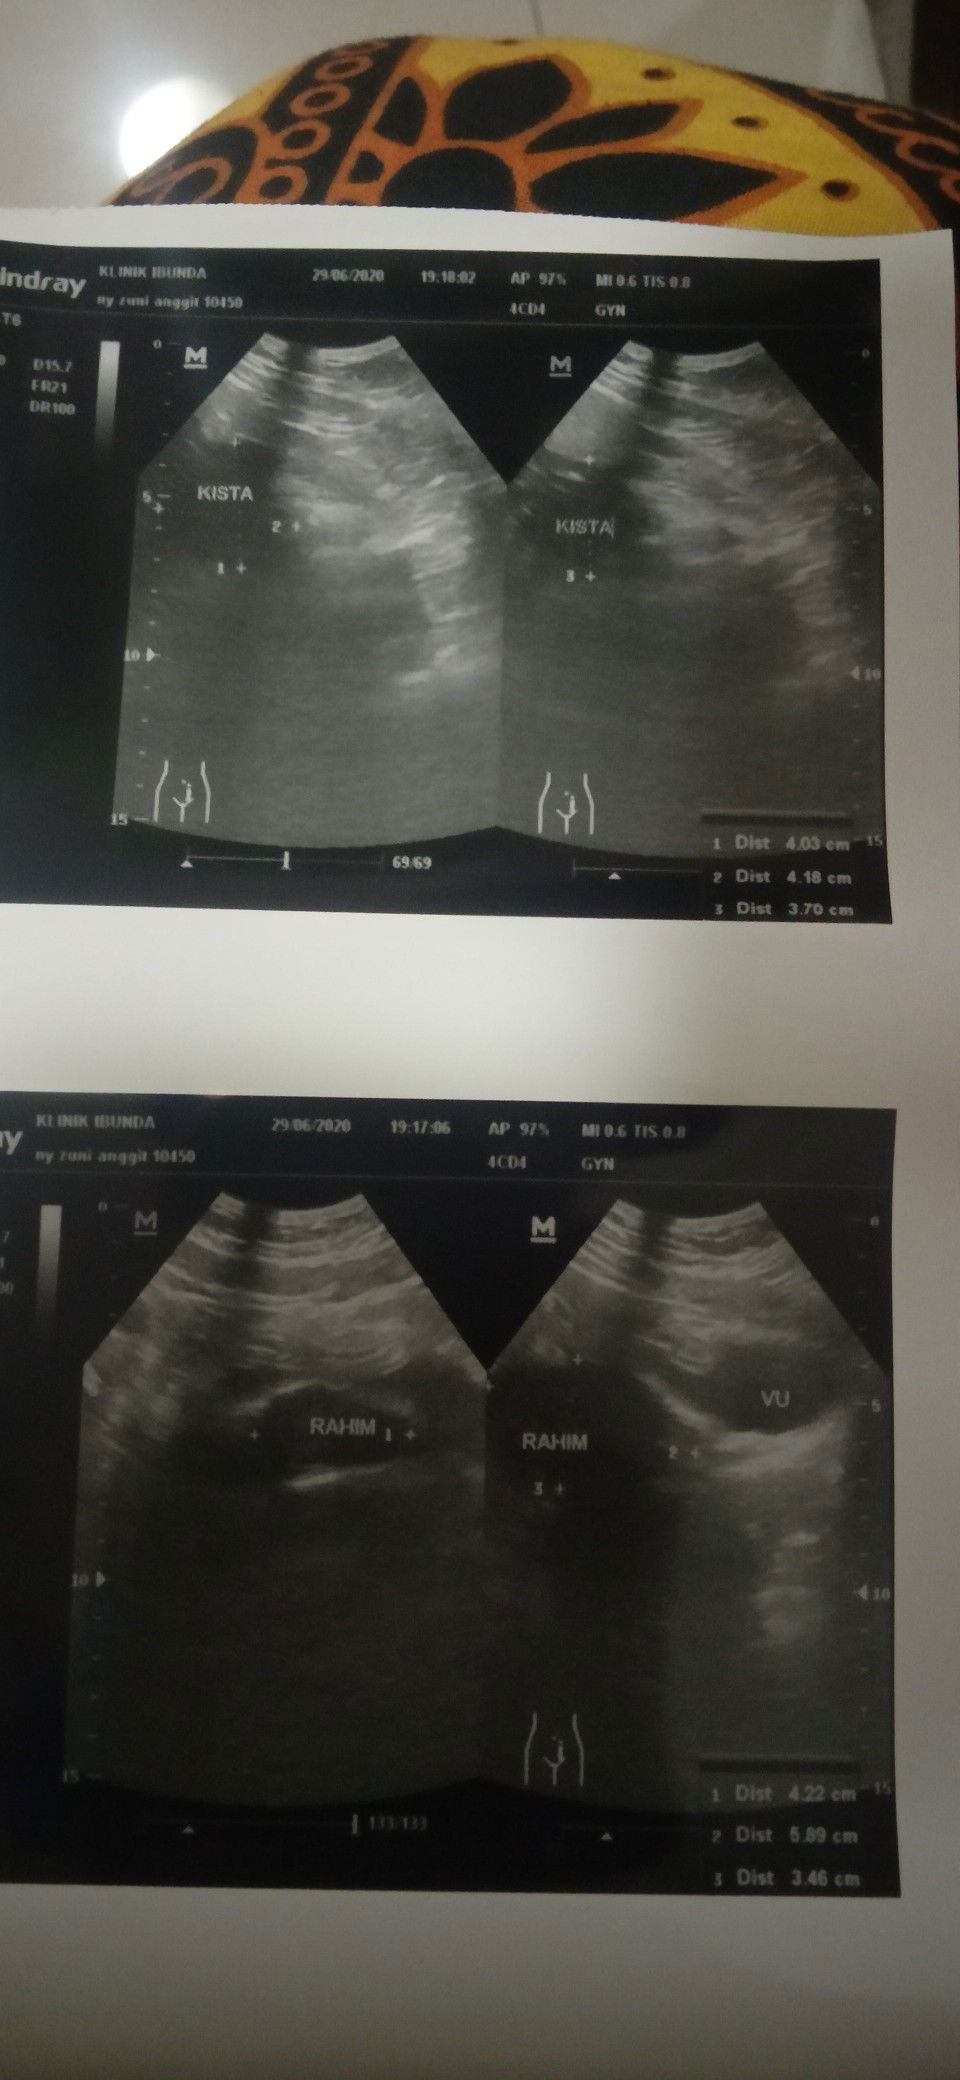

Kista ovarium 4 cm

Well, tadi malam aku pergi klinik karena perut terasa sakit banget, sampai klinik curhat sama susternya akhirnya suruh ngantri... Setelah Berjam" ngantri akhirnya bisa ketemu dokter dan di USG, yang aq kaget aq tu punya kista dan itu udah 4 cm cukup besar kan .. tapi aku ngak ngerasain apa" cuma kemaren tiba" sakit perut sampai gak ketahan.. Dokter nyaranin buat operasi kista aku sih, tapi berhubung tadi malem Dateng nggak sama suami jadinya baru di kasih obat nyeri dan obat untuk kecilin kistanya.. Kalau besok aq kontrol lagi baiknya sama suami nggak ya Bun?? Juga kalau dokter saranin di operasi apa rawat jalan pakai obat aja ya ??? Mohon pencerahannya ya Bun..